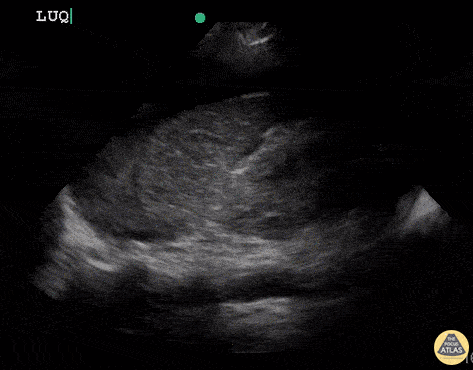

OB/Gyn - Uterine Rupture (Positive FAST)

21 year old female that was having prolonged labour and pain, presented in shock and delivered a non-viable fetus with minimal amount of blood loss from vagina. Continued to be hypotensive and became altered requiring intubation and crash central line. RUSH (including FAST) exam performed to determined etiology of undifferentiated shock. FAST revealed free fluid in abdomen and pt was taken to the OR with GYN and Trauma Surgery. Found to have uterine rupture in OR. Dr. Sathya Subramaniam, Pediatric EM Fellow - Kings County/SUNY Downstate